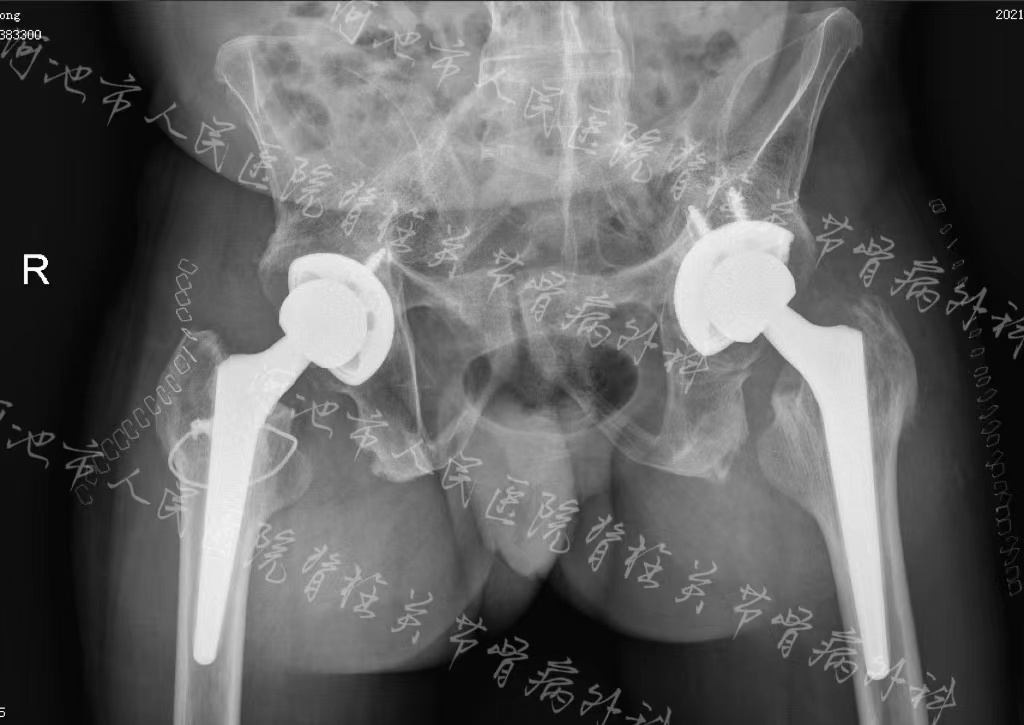

术前影像学检查结果提示:强直性脊柱炎,累及双髋关节

手术当日,麻醉科采取清醒下全麻插管和术中监护,在脊柱关节骨病外科团队的详细设计、精确操作以及手术室护理组的全力配合下,经过3个小时的手术,成功为患者完成双侧人工髋关节置换,解除了双侧髋关节强直的问题,髋关节功能得到极大改善,并且腰背部的紧张感及双下肢屈曲挛缩也得到了缓解,术后康复治疗师细心指导康复锻炼,让患者生活质量明显改善,为后续脊柱矫形手术打下了很好的基础。

术后影像学检查结果